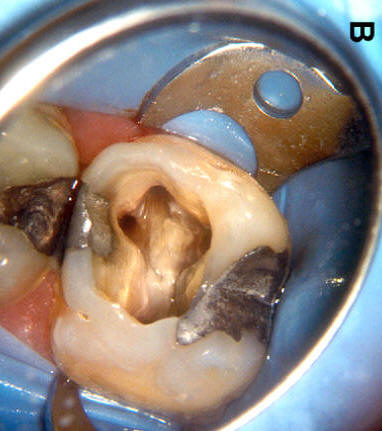

Cuarto conducto en molares superiores (Color amarillo conducto mesio-palatino)

La raíz mesiovestibular es achatada en sentido mesiodistal y amplia en sentido vestibulopalatino.El conducto mesiovestibular con frecuencia es curvo y de sección en forma de hendidura. La existencia de dos conductos en esta raíz, puede presentar la siguiente configuración:

• uno vestibular (Color azul)

• y el otro palatino (Color amarillo)

Estos conductos pueden unirse a distintos niveles, terminando en un foramen único o ser de trayectoria independiente hasta el ápice y terminar en forámenes separados. Son atrésicos y de difícil tratamiento en especial el palatino.